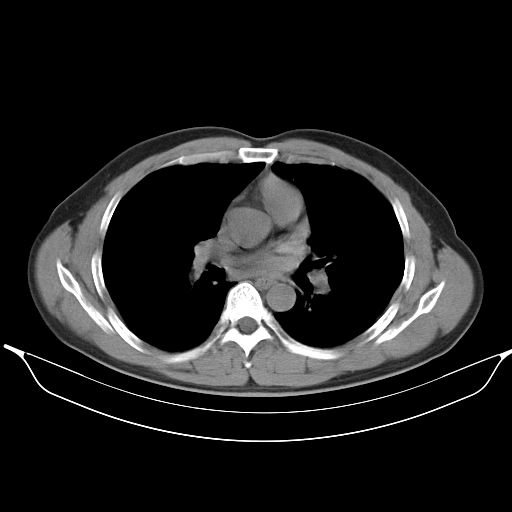

标题: CT25490:男,40岁,体检发现;无其它不适。 [打印本页]

标题: CT25490:男,40岁,体检发现;无其它不适。

考虑右下肺周围性肺癌并肺内多发转移,纵隔淋巴结转移!

支持 !考虑右下肺周围性肺癌并肺内多发转移,纵隔淋巴结转移,(气管前腔静脉后,隆突下,主动脉弓下都有了)